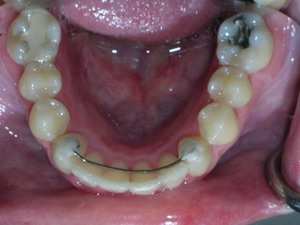

This case was of a young lady who desperately wanted Invisalign, but had been told it was not possible. There was not one, but two teeth that had come in toward the roof of the mouth.

And more.

Needless to say, we were both quite happy with the outcome. Using elastics we were able to push back the back teeth and create space for the two teeth stuck behind.